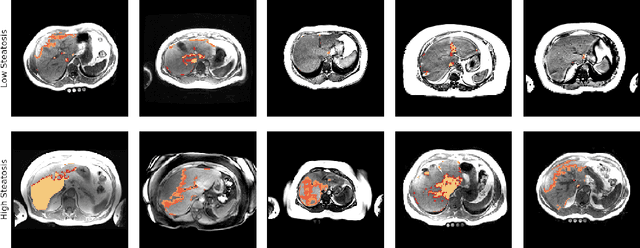

Abstract:Predictive marker patterns in imaging data are a means to quantify disease and progression, but their identification is challenging, if the underlying biology is poorly understood. Here, we present a method to identify predictive texture patterns in medical images in an unsupervised way. Based on deep clustering networks, we simultaneously encode and cluster medical image patches in a low-dimensional latent space. The resulting clusters serve as features for disease staging, linking them to the underlying disease. We evaluate the method on 70 T1-weighted magnetic resonance images of patients with different stages of liver steatosis. The deep clustering approach is able to find predictive clusters with a stable ranking, differentiating between low and high steatosis with an F1-Score of 0.78.